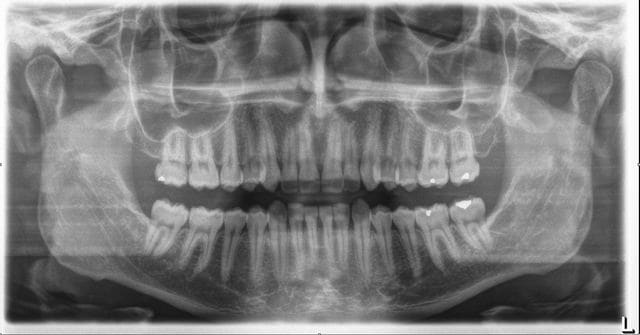

Extraction des 38-48 sous AG il y a 2 ans. Se plaint d'halitose depuis, avec parfois inflammation gingival vers le trigone.

Poche dans l'angle disto-vestibulaire de 37 d'au moins 5mm. Etat global tissulaire OK.

Il semble que 37 ait pris un coup de fraise.

C'est pas un coup de fraise c 'est typiquement la carie en distale de la 7 crée par la DDS.